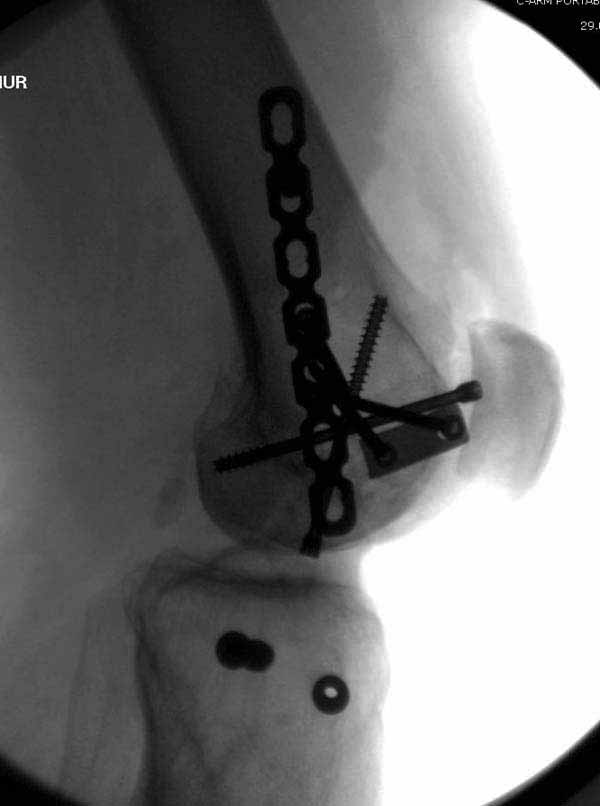

У больных как в этом случае, с вовлечением двух мыщелков правильно, что сделали вытяжение до операции. Здесь имеется флексионный компонент на другой стороне, и я бы рекомендовал операцию делать из двух доступов. Сперва фиксировать медиальную колонну custom made пластиной, обычно 1/3 тубулярной пластиной в 4.5 мм, потому что пока производители опаздывают с медиальной пластиной.

Пластину надо устанавливать на апексе перелома, иначе фрагмент начнет сползать. А на второй стороне, если имеется большой одиночный фрагмент тогда проблем не бывает, и их можно собрать компрессирующими винтами. Проблема наступает тогда когда многофрагментраность на латеральной стороне, где надо применить комбинированный метод, иногда несколькими пластинами. Или сменой позиции установки пластины, чтобы максимально прикрыть перелом и создать боковую поддержку.

Здесь пример медиальной пластины и латеральный комбинированный метод (у второго больного старый перелом тибиал плато, леченный где то и когда то)